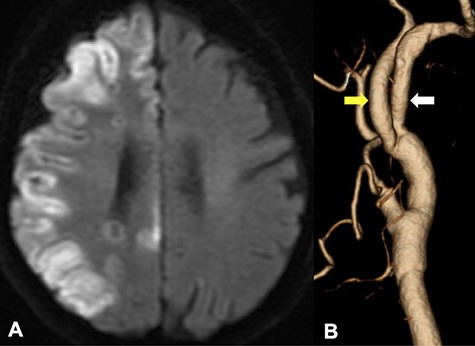

DWI in MRI demonstrated the new ischemic brain lesions on DWI 1 day after CEA in the right cerebral hemisphere cortex of the right ICA region (A); CTA demonstrated favorable patency of all arteries with an improvement of the internal carotid stenosis (B, yellow arrow: ICA, white arrow: PPHA).